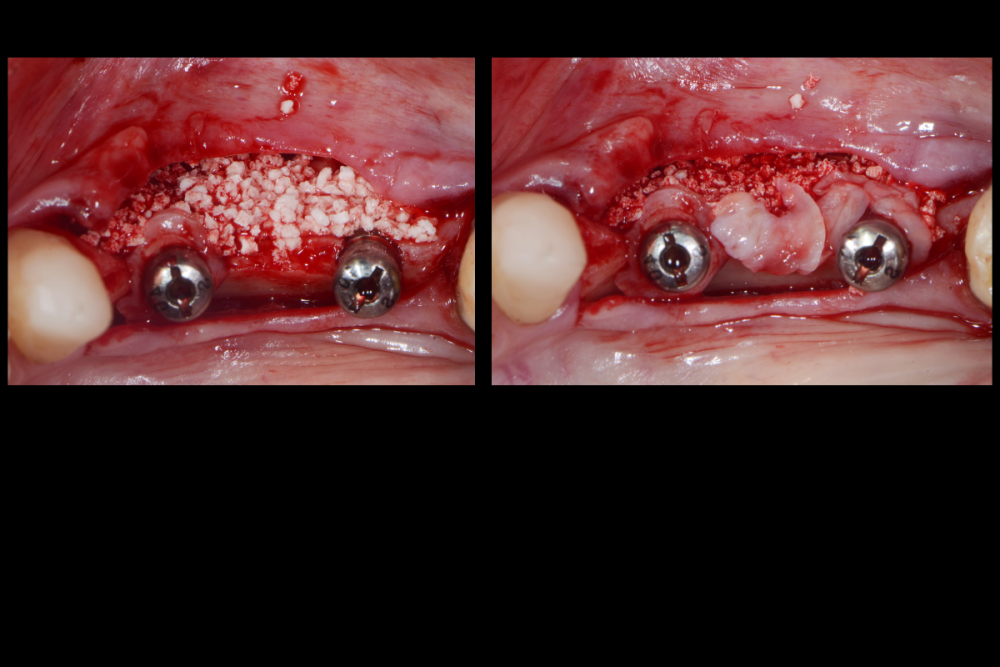

АнтонТЛТ Опубликовано 11 февраля, 2022 Поделиться Опубликовано 11 февраля, 2022 Мембраны под рукой не было? Ссылка на комментарий

Карен Аванесов Опубликовано 11 февраля, 2022 Автор Поделиться Опубликовано 11 февраля, 2022 6 минут назад, АнтонТЛТ сказал: Мембраны под рукой не было? Всегда в запасе. но не в этот раз. Ссылка на комментарий

АнтонТЛТ Опубликовано 12 февраля, 2022 Поделиться Опубликовано 12 февраля, 2022 7 часов назад, Карен Аванесов сказал: Всегда в запасе. но не в этот раз. Я при таких сюрпризах делаю мобилизацию язычного лоскута, вестибулярный не мобилизирую, фдм вторым этапом. Что на 4 слайде справа? Ссылка на комментарий

Irouil Опубликовано 12 февраля, 2022 Поделиться Опубликовано 12 февраля, 2022 Кажется, там какой-то алографт на который сверху подсыпан ксено можно ли проследить вывод из работы, что лучше «без», чем «с»? Ссылка на комментарий

Карен Аванесов Опубликовано 12 февраля, 2022 Автор Поделиться Опубликовано 12 февраля, 2022 15 часов назад, АнтонТЛТ сказал: Я при таких сюрпризах делаю мобилизацию язычного лоскута, вестибулярный не мобилизирую, фдм вторым этапом. Что на 4 слайде справа? Делал и так ка ты написал. коллаген 15 часов назад, Irouil сказал: Кажется, там какой-то алографт на который сверху подсыпан ксено можно ли проследить вывод из работы, что лучше «без», чем «с»? Именно! и не только. Полезно смотреть старые работы. только не все пациенты исправно приходят Ссылка на комментарий